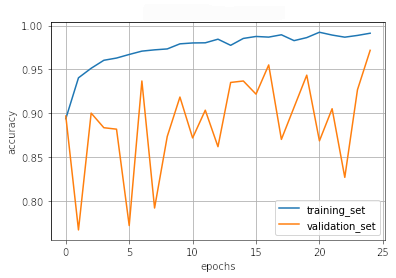

III.2 Classification results

The training procedure in all scenarios has converged. Looking at the evolution of training and validation accuracy (Fig. 11a) indicates that a larger validation dataset would be beneficial. To stabilise the classifier training a procedure of multiple training runs to select the best model is used (Materials and methods). Resulting classifiers are able to discriminate between classes with good precision, for example, see the confusion matrix of the best overall model presented in Fig. 11b. It can also be seen that for the normal class, the rate of misclassified images as COVID-19 ones is higher than for other classes. This effect is present for all models although smaller for the ones based on the EfficientNet-B0 architecture. In addition, the EfficientNet-B0 variants excel if the correct classification of viral pneumonia class images with the smallest rate of errors. However, the EfficientNet-B0 GAN augmentation scenario shows increased misclassification of healthy images which leads to a poor performance. The evolution of the training accuracy as well as confusion matrices for all models are summarised at the end of this section.

Training results for the two architectures are summarised in Figs. 13, 14, 15, 16, and Table 3. For each architecture four scenarios are considered as described in Training process part of the Materials and methods Section.